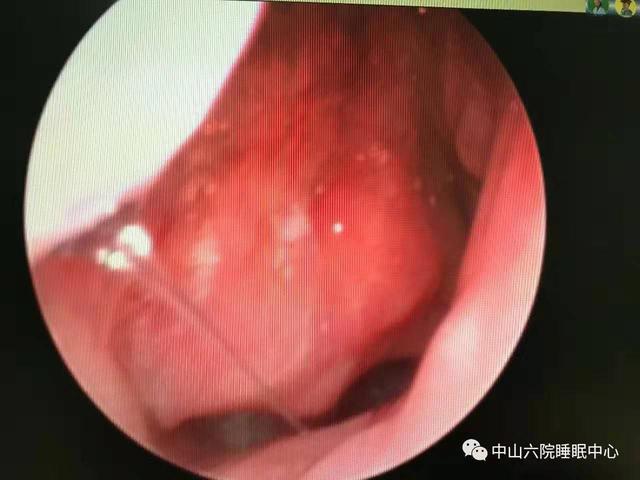

听了女孩的叙述,张湘民赶忙为她举行 了鼻内镜检查和联系CT增强扫描。鼻内镜检查效果 显示,患者右侧鼻咽可见重大 肿物,堵塞了后鼻孔且已经侵占 到左侧鼻咽部!

原来鼻子不惬意 、睡眠打鼾的缘故原由 竟然是肿瘤!凭证 多年临床履历 ,张湘民判断,女孩患上的可能正是广东人群中最多见的鼻咽恶性疾病——鼻咽癌。